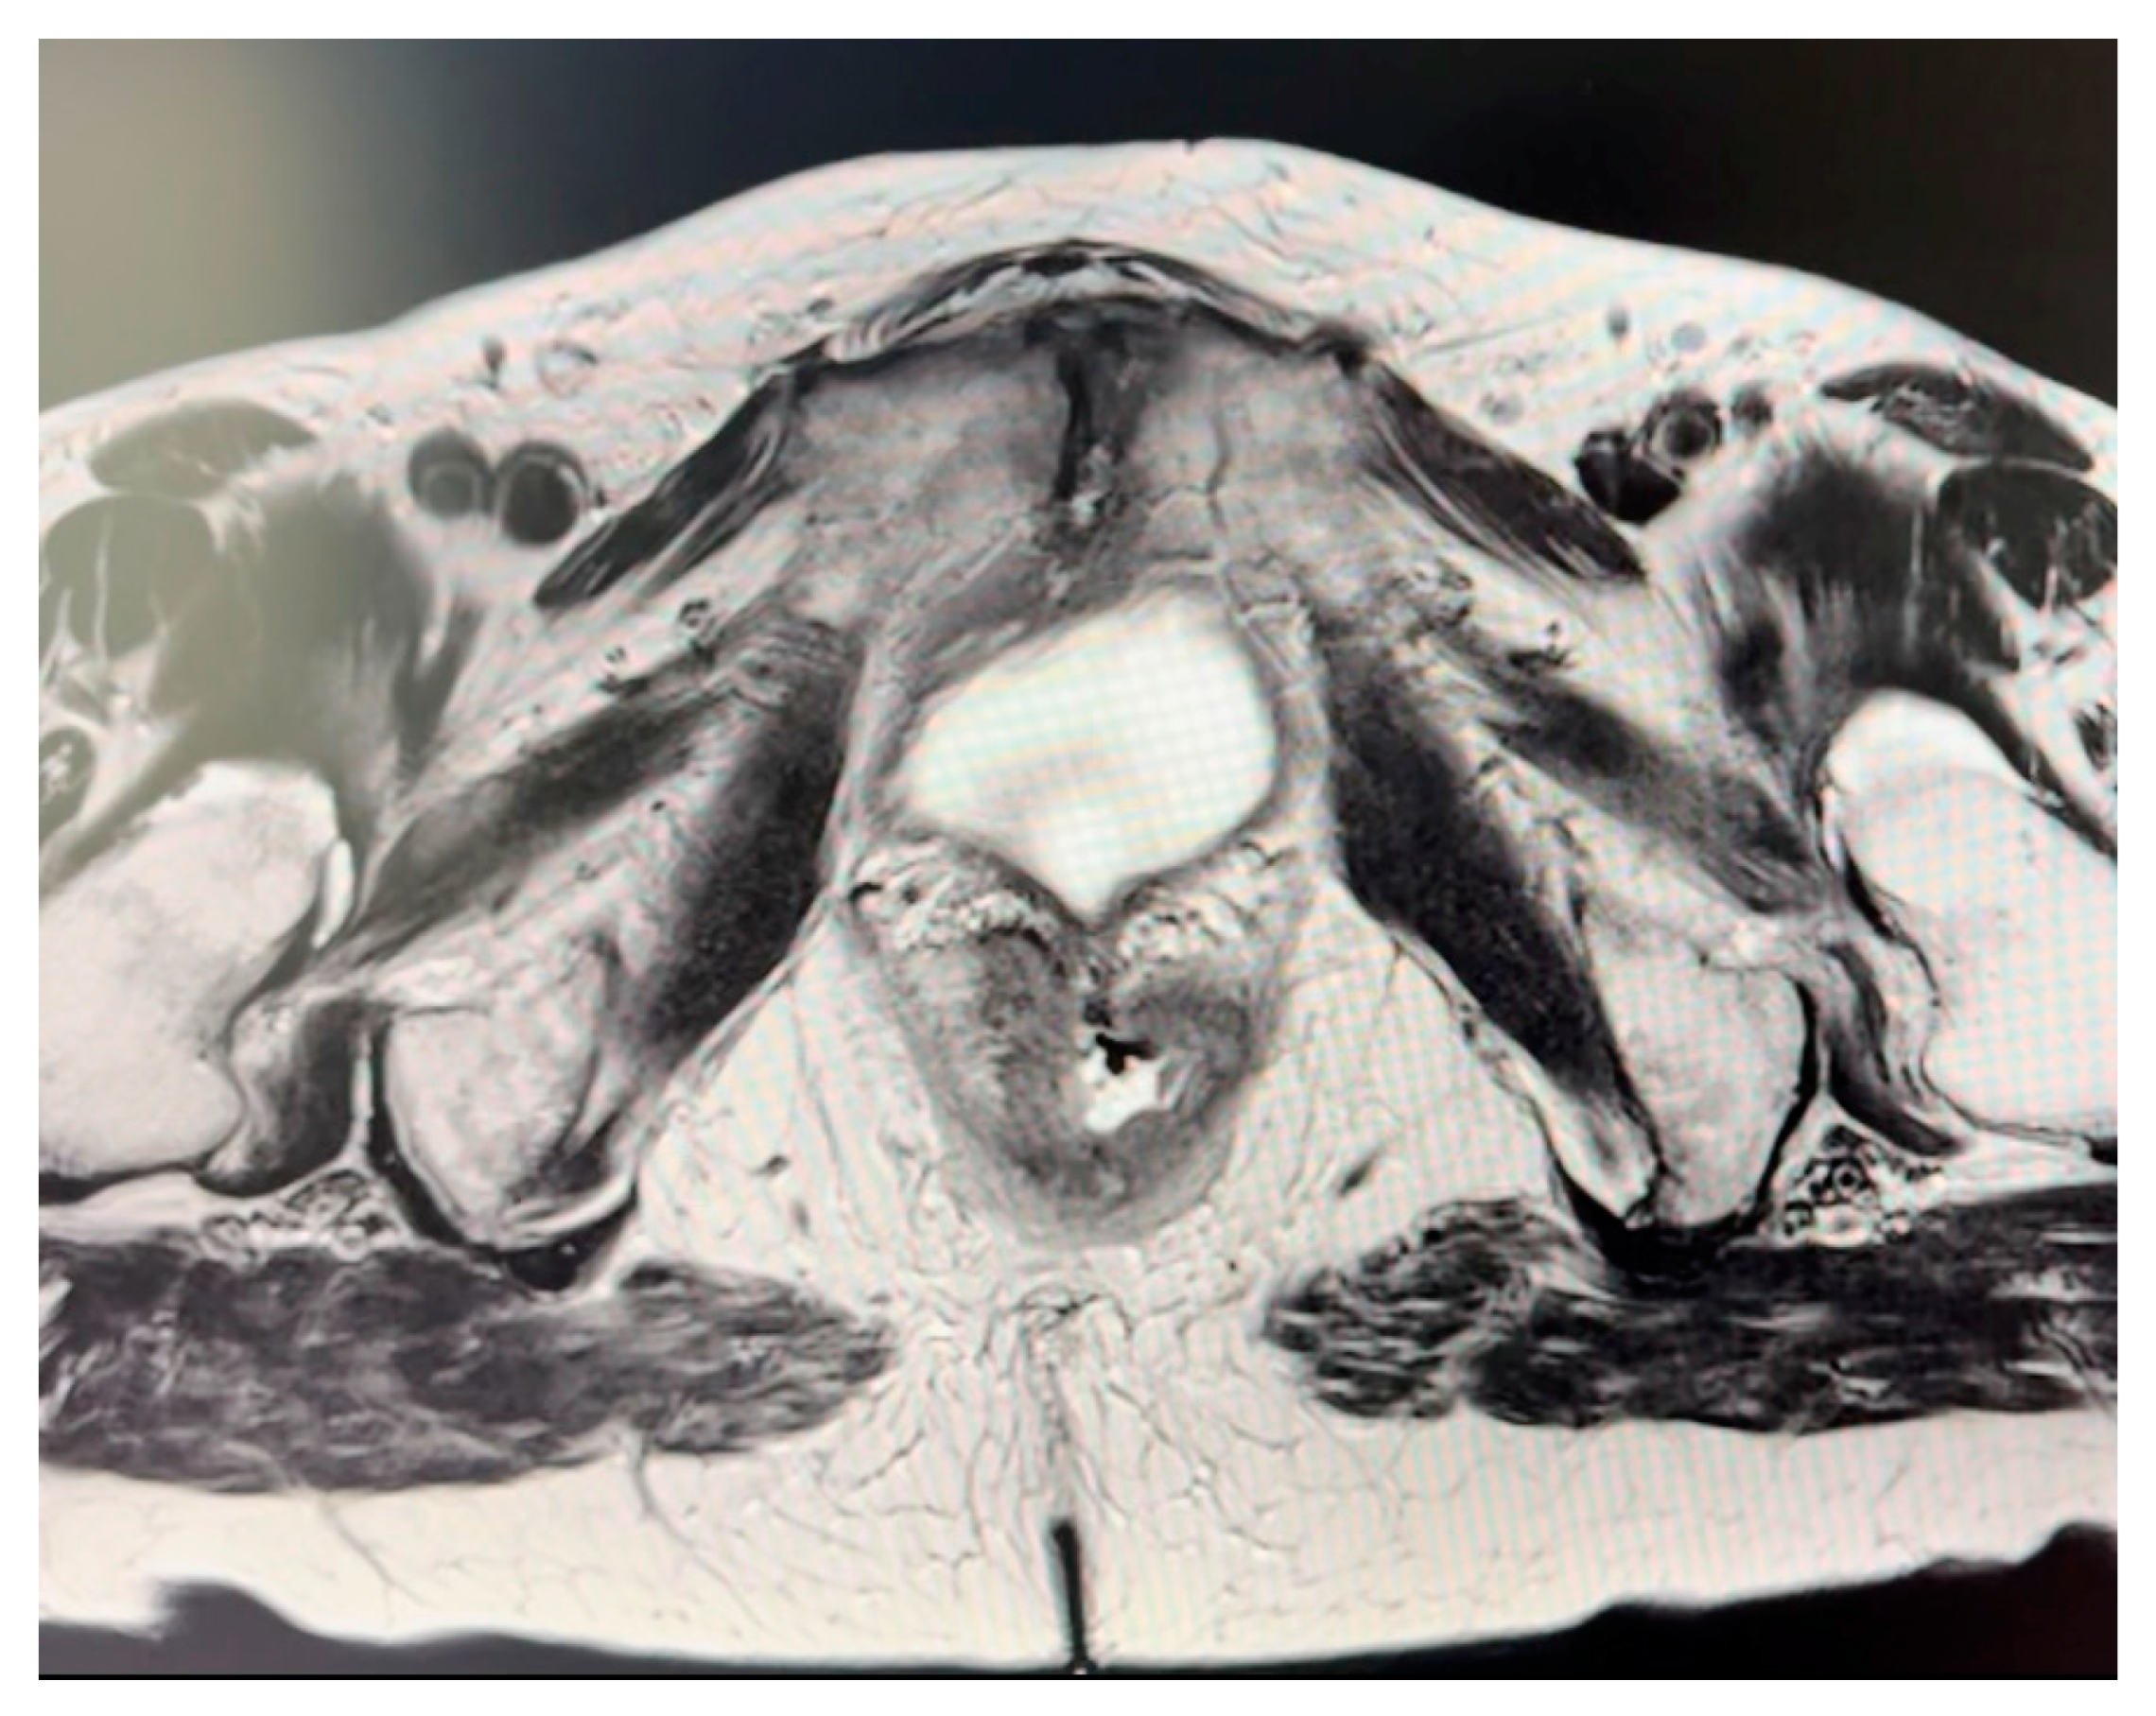

Figure 2.

Magnetic resonance imaging (MRI) of the anal canal showing fistula formation into the vagina.

Indications for perineal reconstruction were invasive squamous anal carcinoma in two cases and adenocarcinoma of the vagina with infiltration of the anal canal in one case, as summarized in Table 1. The average size of resected tumor was 10.3 × 5.2 × 5.1 (range, 13.5–7.6 × 7–3.8 × 7.5–2.6) (Figure 2). No local recurrence was documented. Within this case series, one instance of partial tip necrosis of the deep flap with continuous wound discharge was observed and was salvaged with surgical debridement and secondary sutures. All donor incisions healed without complication.